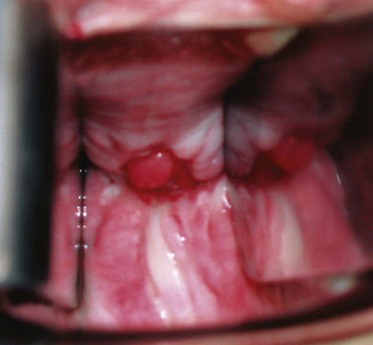

Figure 77–2 Posthysterectomy vesicovaginal fistula (VVF). Retraction with a weighted speculum and Heaney right-angled retractors to provide lateral retraction are needed to visualize this posthysterectomy VVF in a nulliparous woman.

A pelvic exam with a speculum should always be performed in the evaluation of VVF. The bivalved speculum examination usually provides a precise assessment of VVF including the location, size, and number of fistulae. Vaginoscopy has been suggested as an adjunct measure, in some cases, using a modified endoscope to precisely visualize the fistula tract (Redman, 1990). Most commonly, VVF following hysterectomy are located along the anterior vaginal wall at the level of the vaginal cuff (Fig. 77–4). A visual and manual assessment of inflammation surrounding the fistula is necessary, because it may affect timing of the repair. Significant inflammation, infection, or induration around the fistula may mitigate against immediate repair. Relevant vaginal anatomy, including depth, associated prolapse, atrophy, and introital size are carefully recorded, because these may affect the surgical approach to repair. Anatomically, fistulae located high in the vagina, at the level of the hysterectomy cuff in a deep narrow vagina, may be best approached by some surgeons abdominally because a vaginal approach in these patients can be challenging. This may be especially relevant in nulliparous females in whom there is usually very limited pelvic floor laxity or vaginal prolapse. Postmenopausal vaginal atrophy may be treated with preoperative topical estrogen replacement, thereby optimizing the health and vascularity of potential reconstructive flaps. Palpation for masses or other pelvic pathology, which may require attention at the time of fistula repair, is also performed. Notation of prior incisions in the perineum, lower abdomen, and thigh is necessary because these tissues may be required for flap reconstruction when definitive repair is undertaken.

Figure 77–4 Vesicovaginal fistula (VVF) on physical examination. A large VVF is seen at the apex of the vagina after hysterectomy. The VVF in this image is seen as reddish pink bladder mucosa prolapsing into the vagina. Hand-held Heaney right-angled retractors provide lateral retraction in this image.